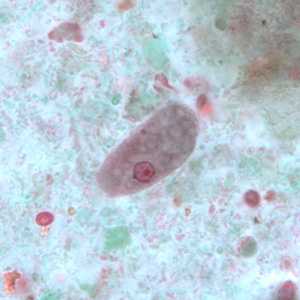

E. polecki trophozoites stained with trichrome.

Figure A: Trophozoite of E. polecki stained with trichrome.

Figure B: Trophozoite of E. polecki stained with trichrome.

Figure C: Trophozoite of E. polecki stained with trichrome.

Figure D: Trophozoite of E. polecki stained with trichrome.

Figure E: Trophozoite of E. polecki stained with trichrome.